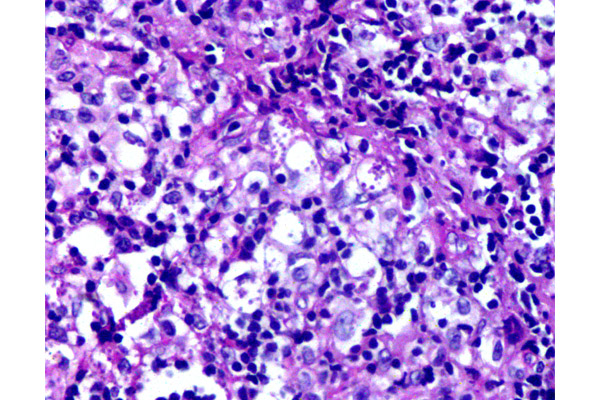

En las fases agudas, la lesión es rica en parásitos y en el infiltrado predominan los macrófagos espumosos cargados de parásitos y una respuesta celular mixta de tipo histiocitaria.

El diagnóstico definitivo requiere la identificación de la forma intracelular del parásito: el amastigote de Leishmania (o corpúsculo de Leishman-Donovan), observados con coloración de PAS, en esta imagen, en las áreas señaladas con elipses.

A mayor aumento se aprecian los macrófagos espumosos cargados de parásitos, teñidos de magenta con coloración de PAS, Estos amastigotes son cuerpos redondos u ovalados, pequeños, de 2 – 5 µm de diámetro, de ubicación intracelular exclusiva.